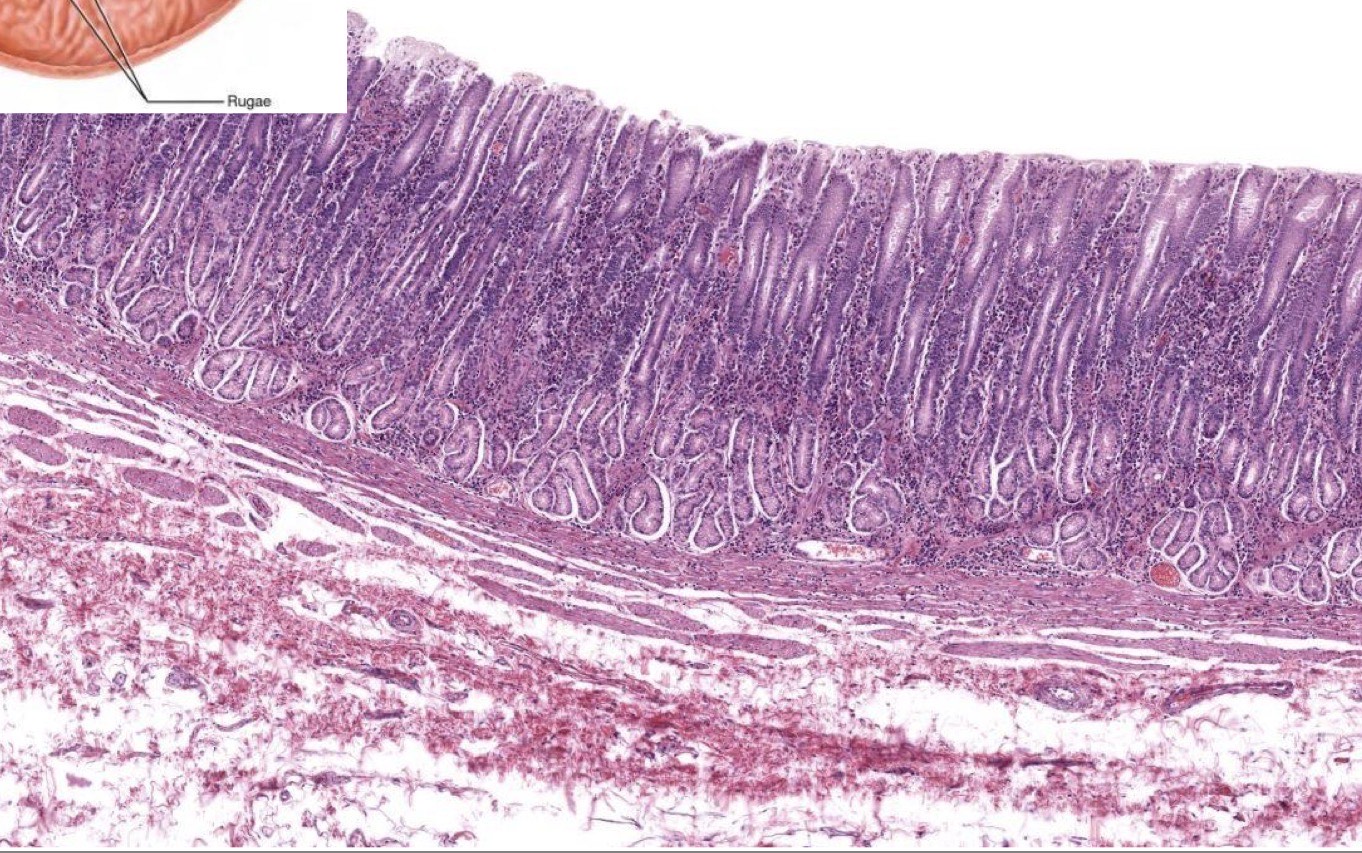

Identify the Structure (be specific)

Rugae in mucosa and submucosa of Stomach

What is the Gastroduodenal Junction?

boundary between the stomach and duodenum, controls passage of chyme.

G in Pyloric Stomach = Mucosa, G in Duo = Submucosa and has villi

Identify the Structure

Gastroduodenal Junction; stomach (Top) duodenum (Bottom)